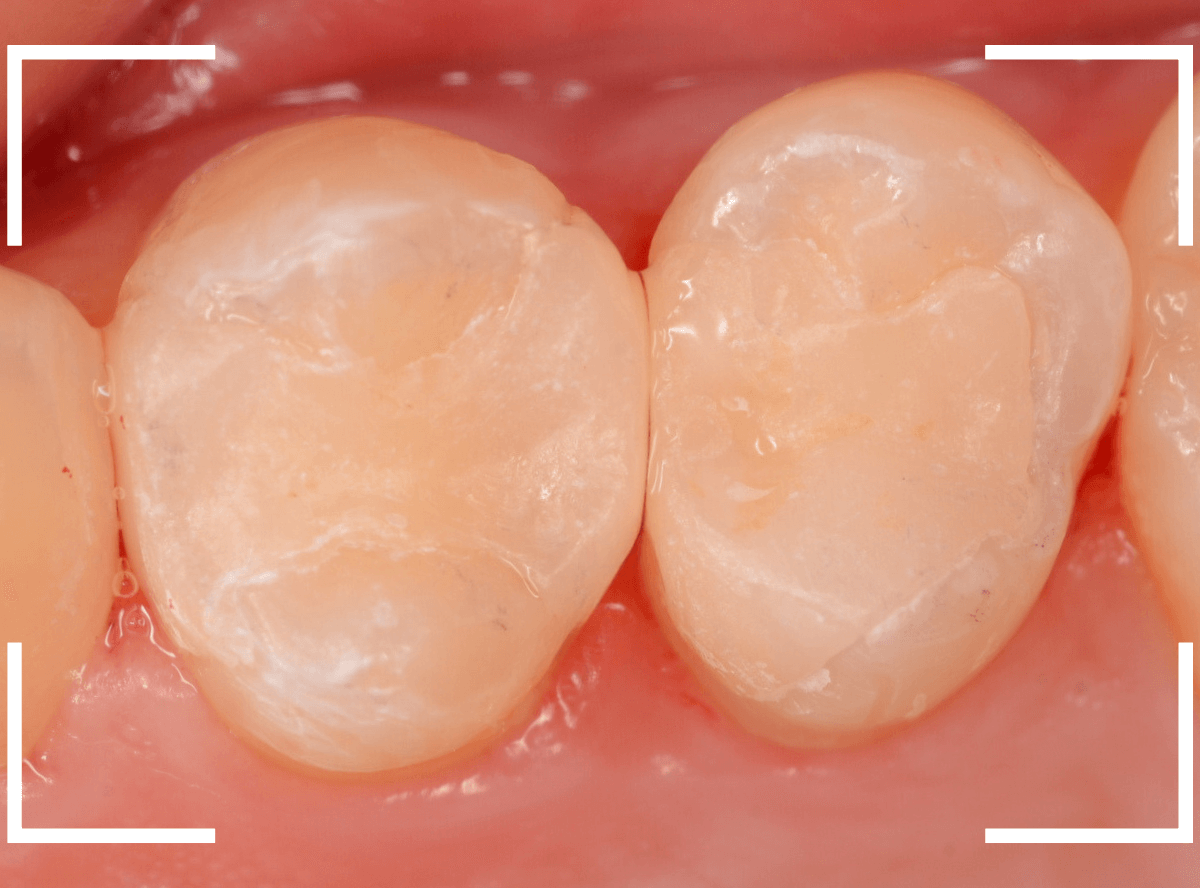

Case.28 虫歯治療後、半年以上来院されなかった患者さん

虫歯を治療して、セメントで歯を削った部分を封鎖した後、再修復を検討中で、半年以上来院されなかった患者さんです。

虫歯を治療して、セメントで封鎖した状態というのは、家でいえば、しっかりした屋根がない状態です。

今回は、セメントの一部がはがれる程度で済んでいましたが、虫歯が再発し、再治療、最終修復物の変更の可能性も出てきます。

治療再開後、セラミックの最終修復を希望されましたので、歯をトリミングし、型取りします。

治療後の状態です。

治療後の定期メンテナンスに来院されない患者さんもまれにいらっしゃいますが、一定期間来院のない方は破折などの際の保証も受けられません。

くれぐれも忘れずに来院していただくようにお話しし、終了となりました。